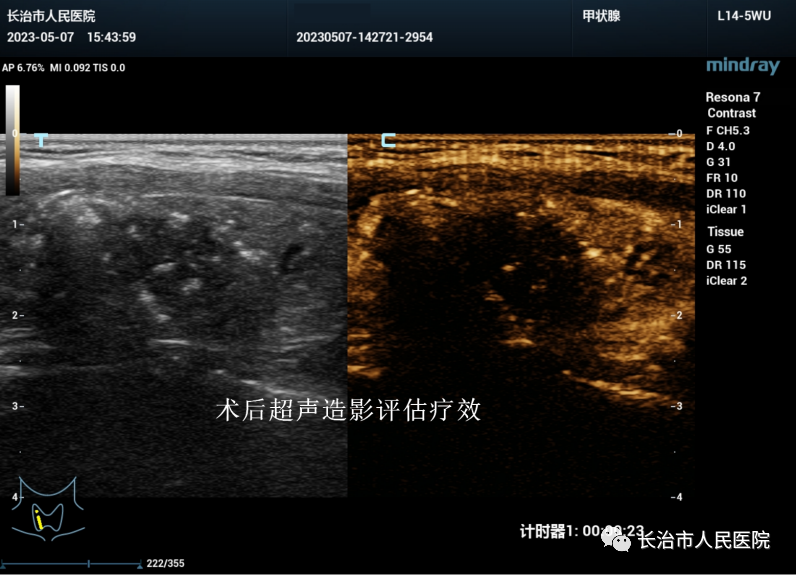

近年来,超声医学技术发展迅猛,尤其是介入超声的发展,迎来了超声从诊断到治疗的里程碑。介入超声以其针过无痕、精准微创等优势获得了临床及患者的认可。10cm大小的肝囊肿,16cm大小的肾囊肿,3cm大小的甲状腺良性结节,0.8cm大小的甲状腺恶性结节,无论其大小良恶,在崔教授精湛的操作技术下,在一根细针的舞动下,在“超声造影”等超声利器的助攻下,短短几分钟或十几分钟,病灶就被“解决”,患者体表只留下一个几乎看不到的针眼。一个巨大肾囊肿患者,术后当场在我院日间手术室门口蹦跳了几下,眉开眼笑,说感觉身体瞬间轻盈了许多。